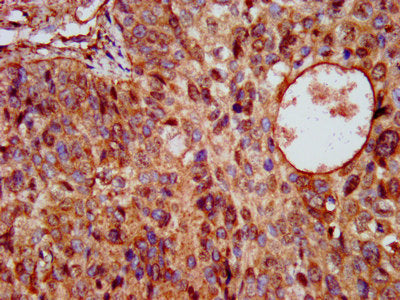

IHC image of the antibody diluted at 1:200 and staining in paraffin-embedded human glioma performed on a Leica BondTM system. After dewaxing and hydration, antigen retrieval was mediated by high pressure in a citrate buffer (pH 6.0). Section was blocked with 10% normal goat serum 30min at RT. Then primary antibody (1% BSA) was incubated at 4°C overnight. The primary is detected by a biotinylated secondary antibody and visualized using an HRP conjugated SP system.

IHC image of KCNE3 Antibody diluted at 1:200 and staining in paraffin-embedded human cervical cancer performed on a Leica BondTM system. After dewaxing and hydration, antigen retrieval was mediated by high pressure in a citrate buffer (pH 6.0). Section was blocked with 10% normal goat serum 30min at RT. Then primary antibody (1% BSA) was incubated at 4°C overnight. The primary is detected by a biotinylated secondary antibody and visualized using an HRP conjugated SP system.